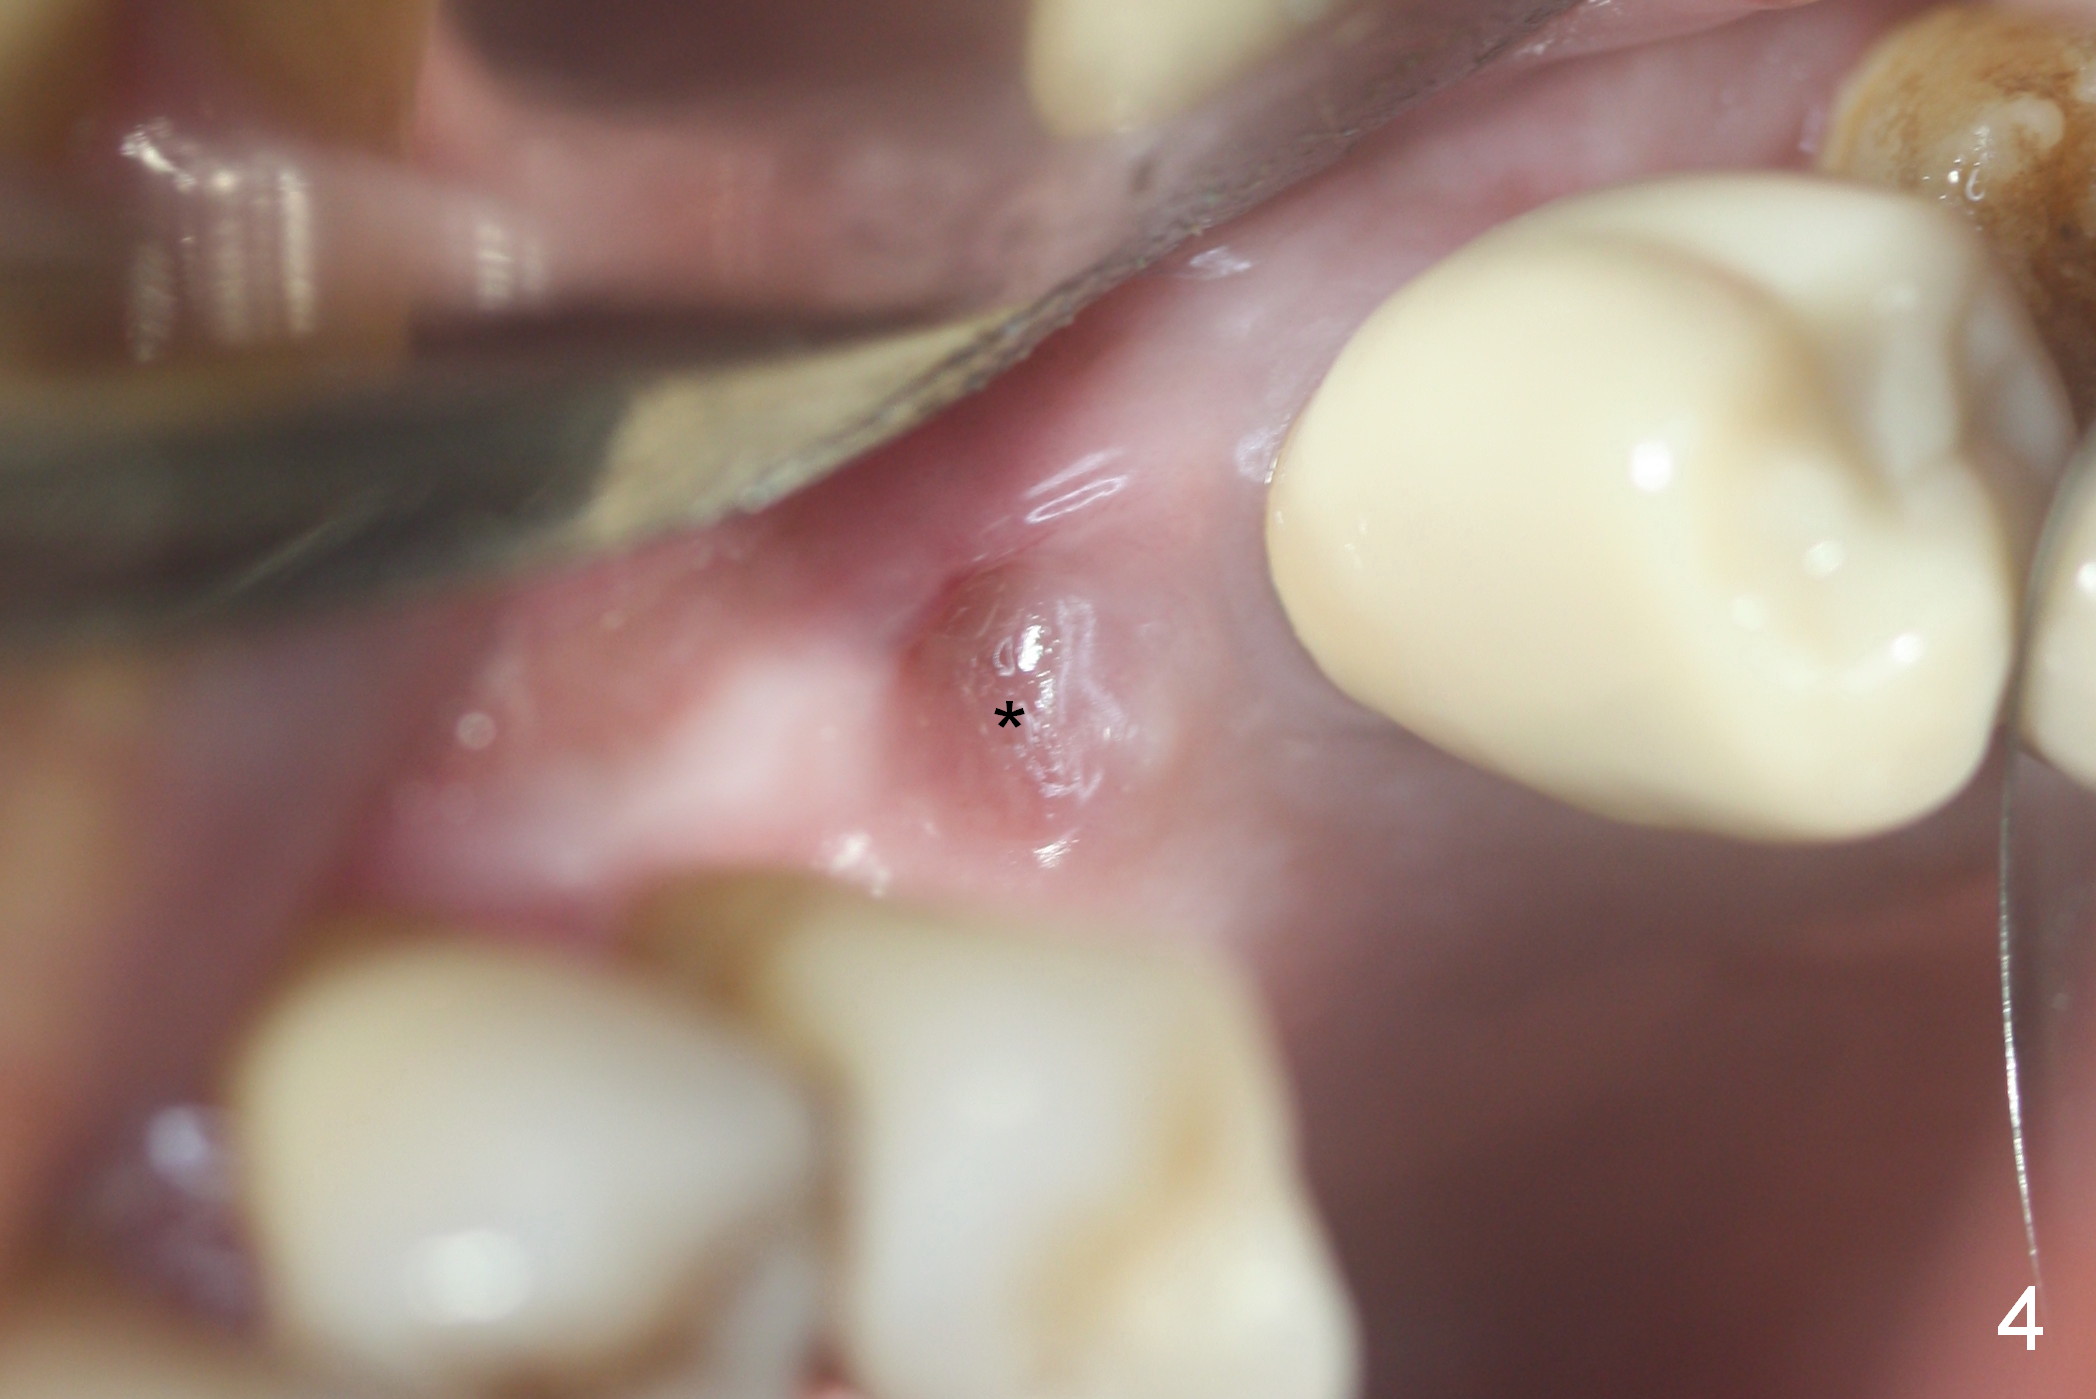

The implant site is healing a few days after loss (Fig.4 *) with a bony defect (Fig.5 ^). It appears that the implant at #14 was placed buccally. An incision is made palatally because of the presence of more keratinized gingiva (Fig.6). The buccal bone height is limited. The soft tissue in the bony defect is lifted into the sinus before bone graft (Fig.7 *).